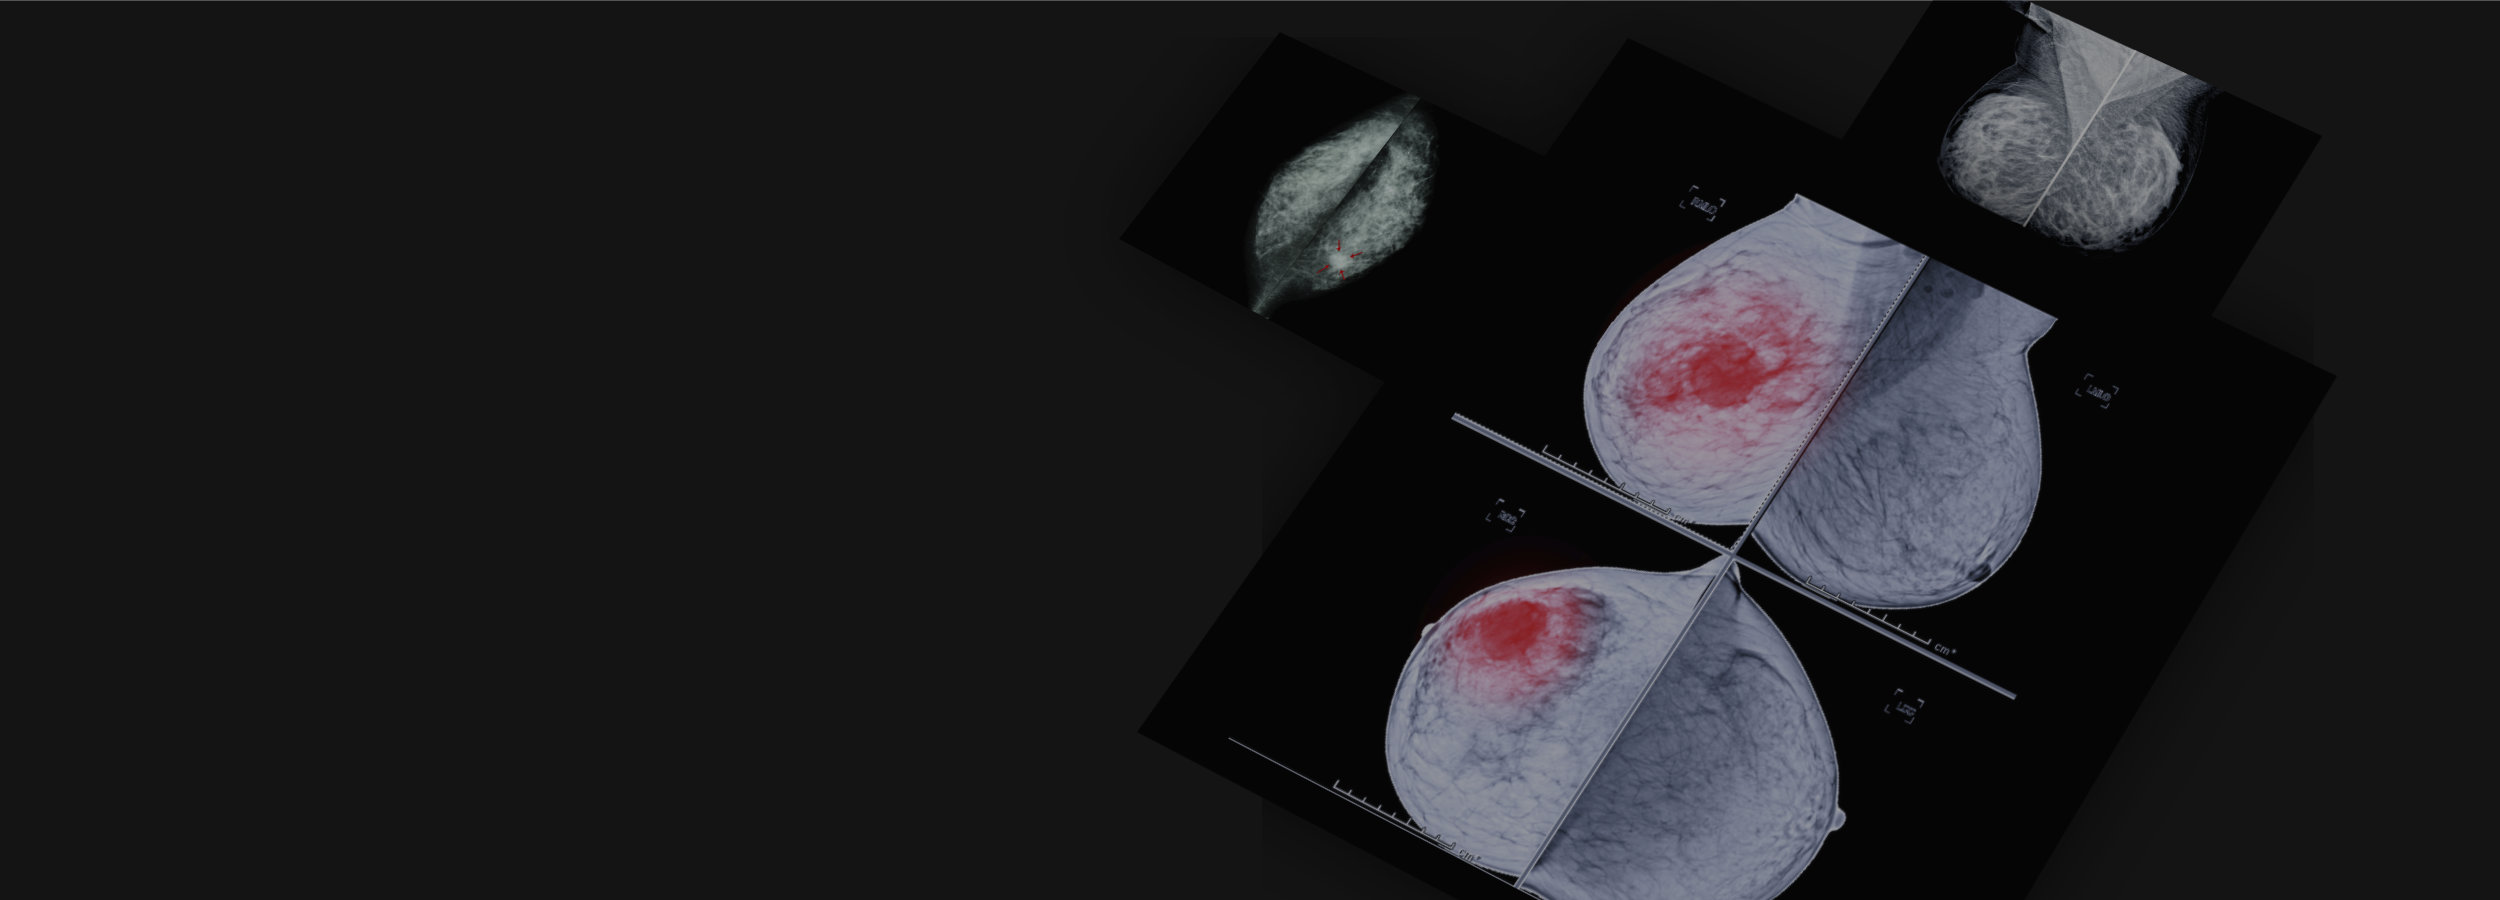

Combination of Artificial Intelligence & Radiologists More Accurately Hmfp Radiology Breast Imaging Breast imaging serves as the primary method for early detection and diagnosis for breast diseases. 65 6789 8883 breast imaging. This includes comprehensive breast imaging, breast cancer genetics, breast cancer surgery, breast pathology and breast cancer oncology. We have a dedicated multidisciplinary team offering the advances in digital mammography, breast tomosynthesis,. Shortens the time taken to. Harvard medical faculty physicians. Hmfp Radiology Breast Imaging.

Mammography AI Tool Cleared This Year Improves Breast Cancer Detection Hmfp Radiology Breast Imaging Shortens the time taken to. Our department’s breast imaging centre is. Harvard medical faculty physicians at beth israel deaconess medical center's (hmfp) department of radiology plays an integral role in supporting. At lifescan imaging, we have a full field digital mammography (ffdm) machine which: We have a dedicated multidisciplinary team offering the advances in digital mammography, breast tomosynthesis,. This includes. Hmfp Radiology Breast Imaging.

Applied Sciences Free FullText TwoStage Deep Learning Method for Hmfp Radiology Breast Imaging Our department’s breast imaging centre is. 65 6789 8883 breast imaging. Breast imaging serves as the primary method for early detection and diagnosis for breast diseases. At lifescan imaging, we have a full field digital mammography (ffdm) machine which: Shortens the time taken to. We have a dedicated multidisciplinary team offering the advances in digital mammography, breast tomosynthesis,. Harvard medical. Hmfp Radiology Breast Imaging.